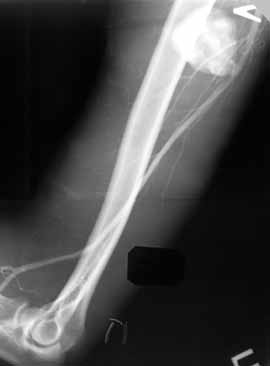

Рис. 4. Посттравматическая ложная аневризма артерии плеча.

Новости лучевой диагностики 1998 4: 32-33